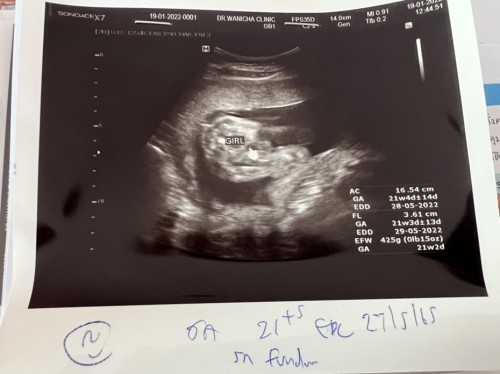

ถ้าไม่อ่านที่หมอเขียน ก็มองไม่ออกเลยค่ะ 😂😂

กำหนดคลอดเดือนไหนคะแม่

พฤษภาค่ะ